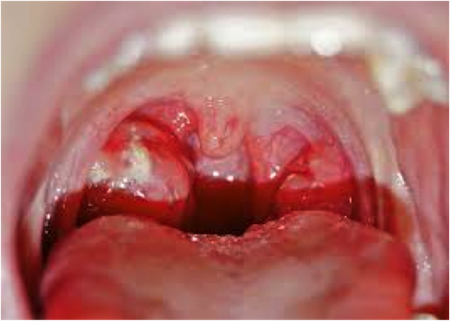

Chronic Throat Inflammation Causes

Common throat Infections: A Review - KIMS

Inflammatory Disorders Of Larynx - The Medical Post

Streptococcal pharyngitis. The course will discuss reasons and treatment options for other causes of sore throat. Allergic rhinitis may cause chronic postnasal discharge leading to irritation of the throat causing sore throat. Lymphoid ... Retrieve Full Source